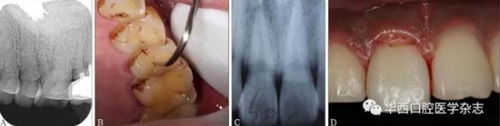

(3)X線片結果具有隱蔽性,需仔細結合臨床檢查進行判斷。如圖3所示,X線片未見折裂線(圖3A),而臨床檢查可見明顯的縱折(圖3B);有時X線片僅顯示1條折裂線(圖3C),而臨床檢查發(fā)現(xiàn)為復雜冠根折(圖3D)。

A:X線片未顯示根折;

B:臨床檢查可見明顯根折;

C:X線片僅顯示1條唇側牙折線,舌側折裂線不清晰;

D:臨床檢查可見右側上頜中切牙出現(xiàn)明顯冠根折。

圖 3 X線片與臨床檢查對比結果